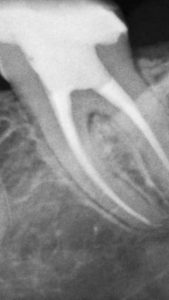

El sistema radiográfico digital New IDA cuenta con un sensor que usa las tecnologías asociadas del CMOS (Complementary Metal-Oxide-Semiconductor), fibra óptica protectora y centelleada. Ese sensor fue fabricado para adquirir la imagen de rayos x digital de alta calidad de la arcada humana y sus estructuras.El proceso de adquisición es realizada posicionado el sensor en la parte interna de la boca atrás de la estructura que se desea realizar el examen.

La estructura debe ser expuesta a una dosis de rayos x usando una fuente externa. Una vez expuesto, el sensor realiza una conversión de los fotones de rayos x en una señal digital y enseguida transfiere para una computadora vía conexión USB (Universal Serial Bus). El software de gestión de imagen dental realiza el interfaz con el sistema New IDA y el usuario, podrá visualizar, mejorar, almacenar, enviar, imprimir entre otras funciones

Es el sensor digital intraoral de DabiAtlante que ofrece imágenes de solución eficiente para obtener un diagnóstico más claro, preciso y avanzado.

Captura imágenes de alta definición en tiempo real.